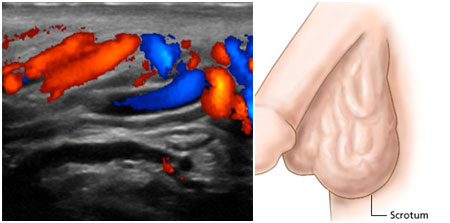

What Is a Varicocele?

A varicocele is a condition where the veins in the scrotum become enlarged and swollen. It occurs when the valves in the veins of the spermatic cord don't work properly, causing blood to pool in the scrotum.